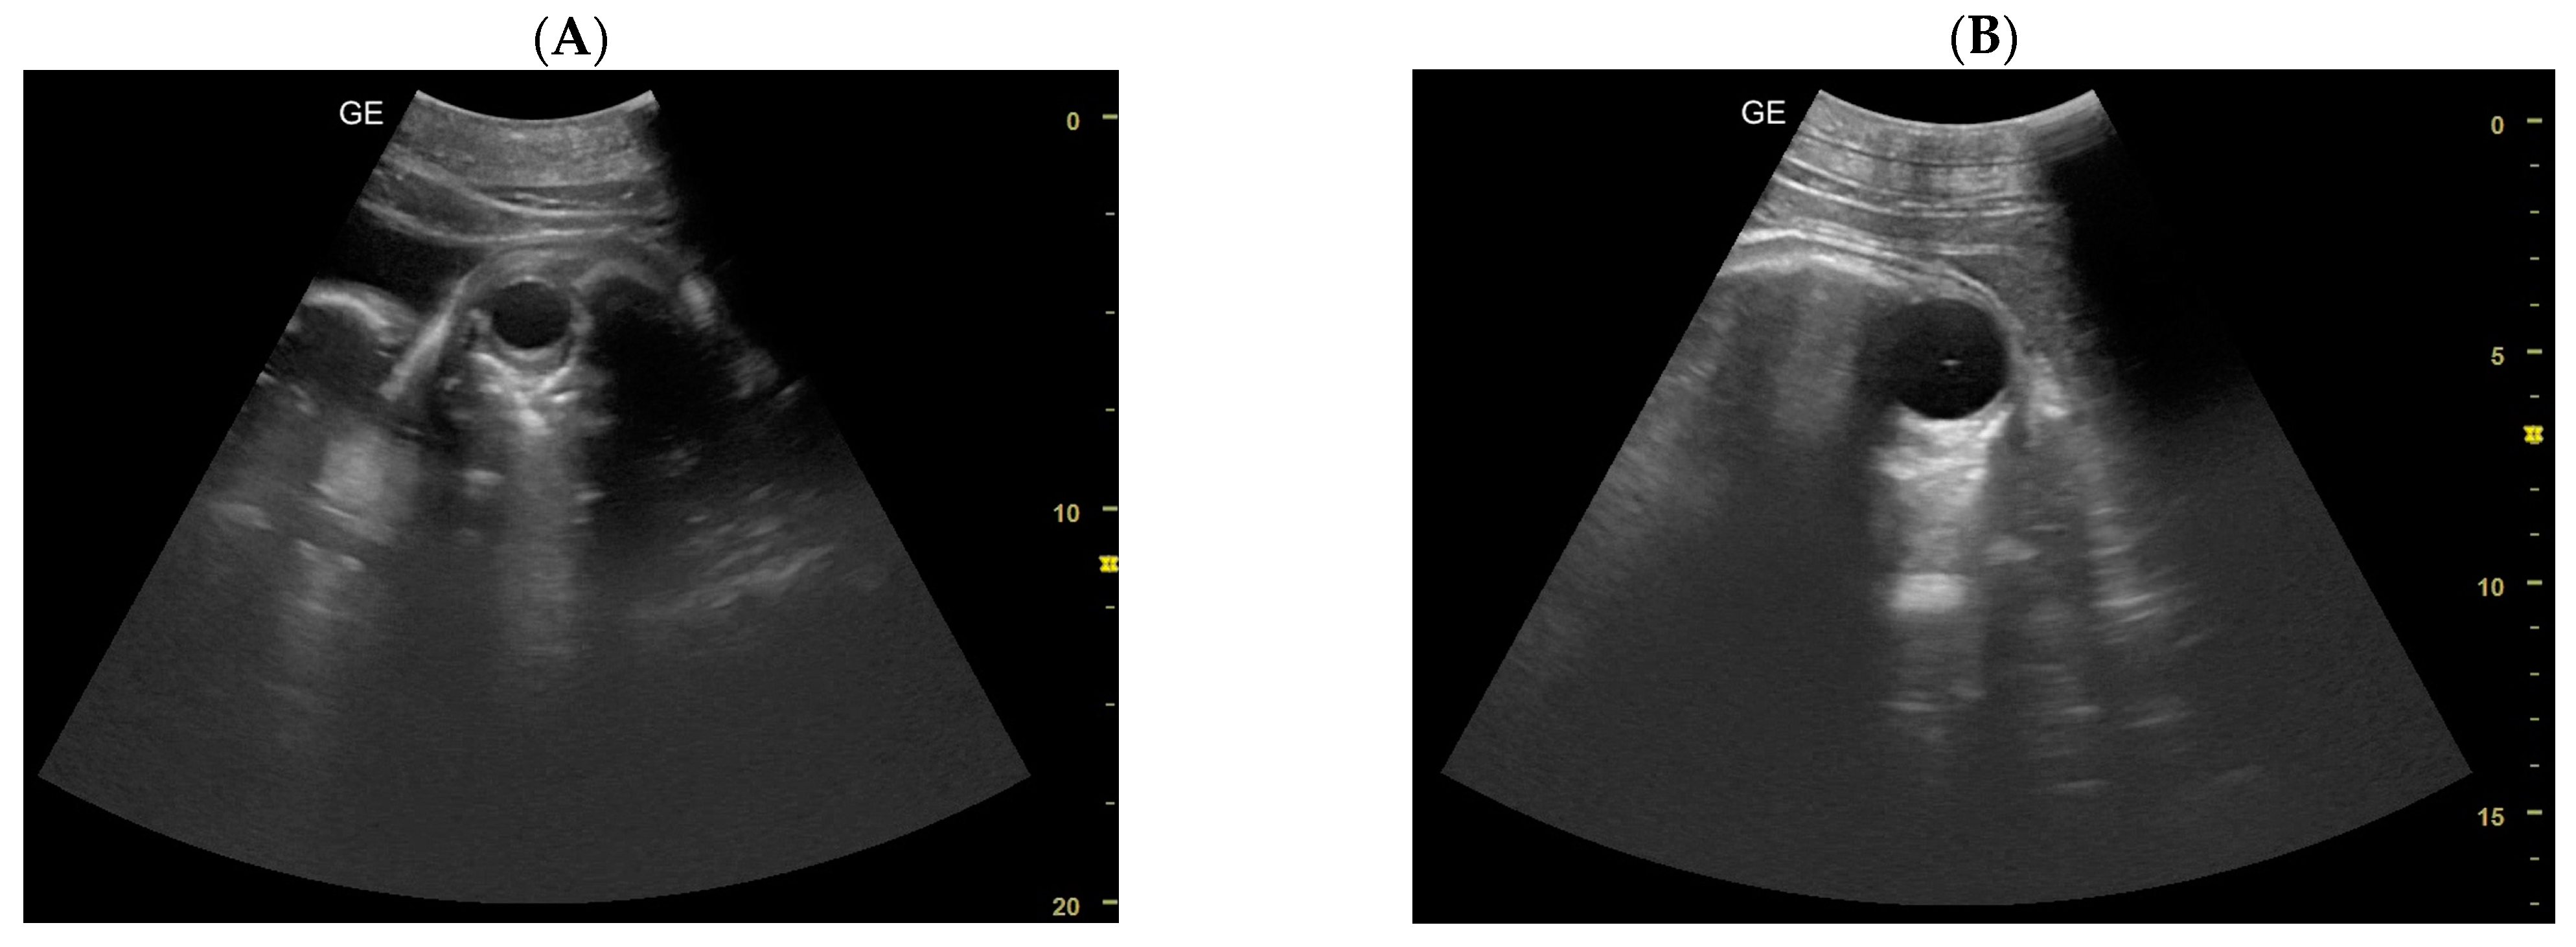

- Day 219 ± 3 days: It is also possible to recognize the eye as an anechoic cavitary structure (Figure 6). During the last month of pregnancy, it is possible to easily identify most of the abdominal organs such as the liver, spleen, intestine, and kidneys (Figure 7). In addition, the genitalia are visible and it could be possible to establish the sex of the fetus: in males, it is possible to identify the penis bone, which is obviously absent in females, but its visualization depends strongly on fetal position.